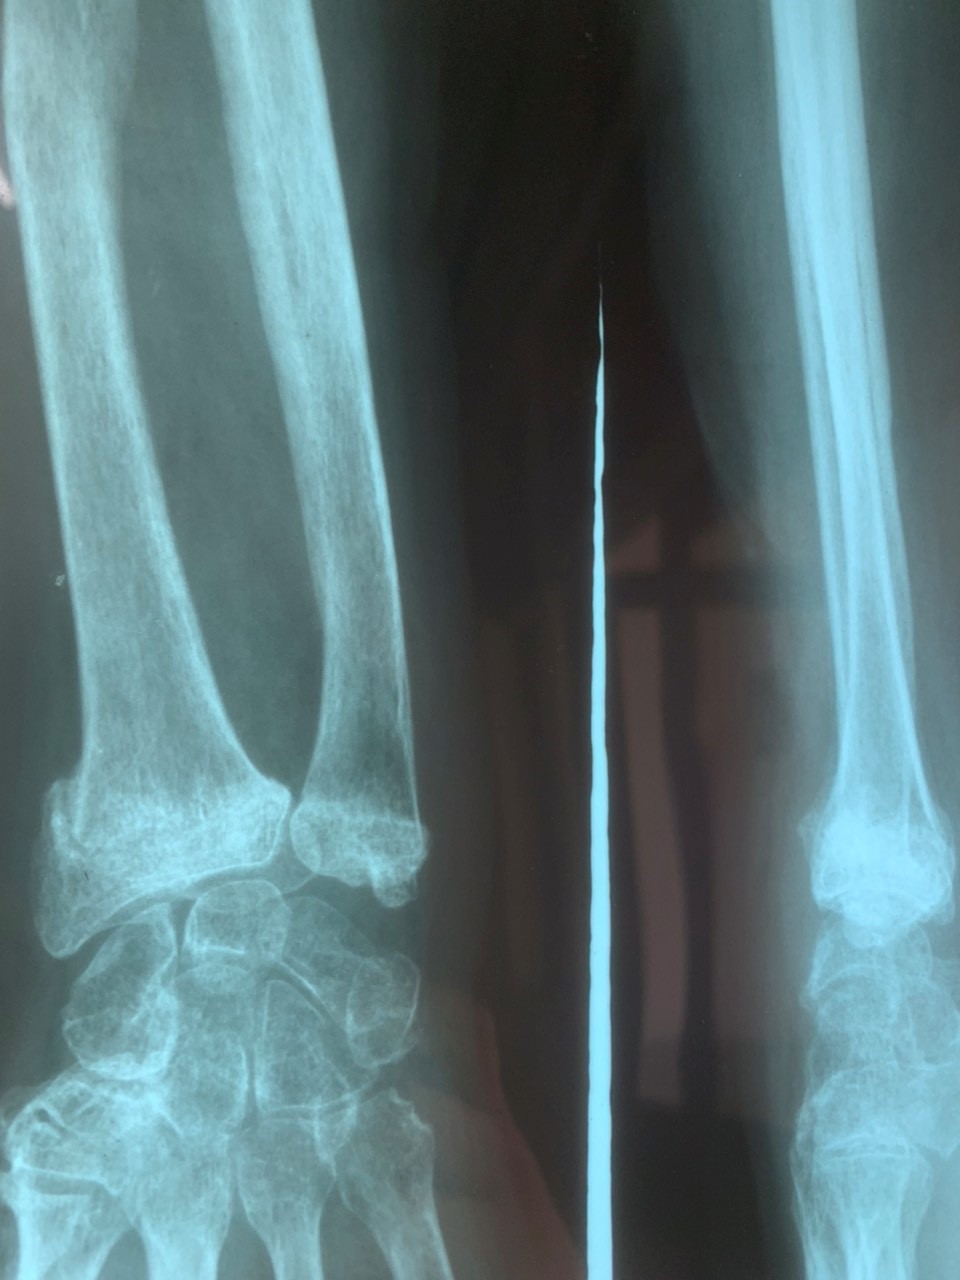

Một số hình ảnh gãy xương cẳng tay